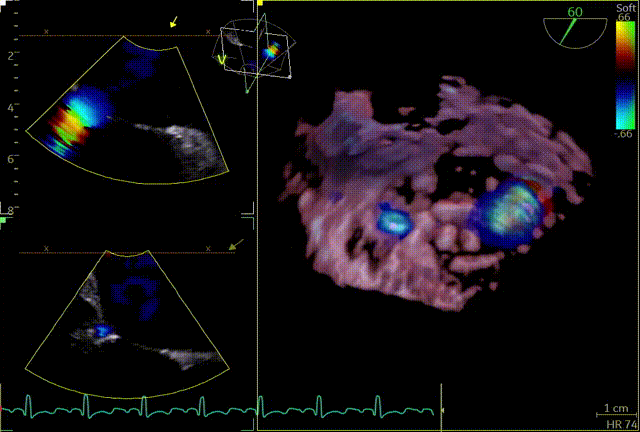

释放后内侧后叶仍旧栓系,反流较重,内外侧都残余反流,内侧为主,考虑到内侧反流较宽,瓣叶够长,栓系难以捕捞,压差不高,第二枚夹子选择XTW,置入第二枚XTW后,在1区上方做轨迹测试,充分释放张力,调整夹子的夹臂方向位于5点-11点的位置,回拉系统,使第二枚夹子位于3区,关小夹子进入到心室侧,由于第一枚夹子起到了稳定瓣叶的作用,第二枚夹子捕捞夹持也异常顺利,一次精准捕获前叶和后叶,再次完整评估二尖瓣夹XTW的方向、组织桥稳定性、瓣叶受限程度及反流减小程度。前后叶Bouncing明显,但是反流却明显增加,开始未明确原因,Orientation,夹持量均无问题,但是内侧还残余反流,考虑内侧可能还要补,决定打开贴近第一个夹子放置,如果有需要内侧再补,此时发现由于患者EF值低,麻醉老师肾上腺素一直在给,心脏搏动较为剧烈,反流术中的异常增多可能是由于此原因导致,遂停止给药。

第二个XTW第一次夹持

第二个XTW第二次夹持

释放后

外侧2偏1区可见后叶栓系,下方空间乳头肌腱索杂多,后叶长度也一般,跨瓣压差3mmHg,第三枚夹子选择了NT,打算靠近第一枚夹子2偏1区夹持,置入NT后,在1区上方做轨迹测试,充分释放张力,调整夹子的夹臂方向位于1点-7点的方向,回拉系统,使第三枚夹子靠近第一枚夹子,关小夹子进入到心室侧,由于第一枚夹子起到了稳定瓣叶的作用,第三枚夹子捕捞夹持相对顺利,一次精准捕获前叶和后叶,再次完整评估二尖瓣NT的方向、组织桥稳定性、瓣叶受限程度及反流减小程度。反流改善到1+-2+,平均跨瓣压差3.85mmHg,左房压明显下降,肺静脉逆流明显改善,手术完美结束。

第三个夹子NT

最终结果

术后肺静脉频谱

术后平均跨瓣压差

术后左房压